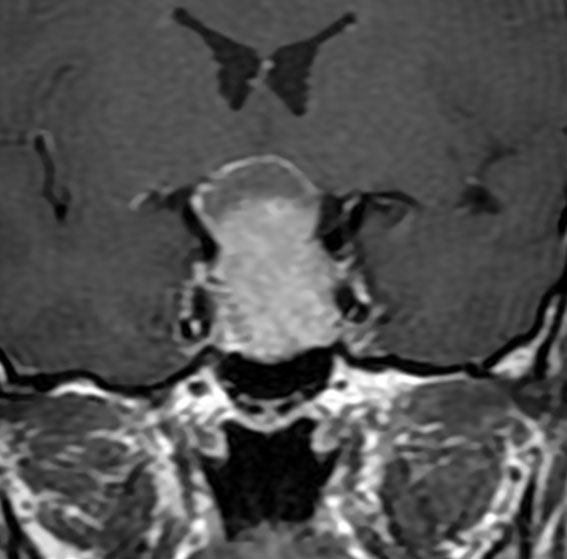

典型的なMRIの画像です

下垂体腺腫のMRIです。両側の視野障害(両耳側半盲)のために手術を受けた患者さんのものです。この腫瘍は非機能性腺腫といってホルモンを出さない腫瘍でした。少し大きめでしたが全部取れて視野の障害はよくなりました。

左の2枚はガドリニウム造影剤を使って写したもので腫瘍の形がよくわかります。右の1枚はT2強調画像と言います。MRIでは撮影の仕方によって見え方が違います。